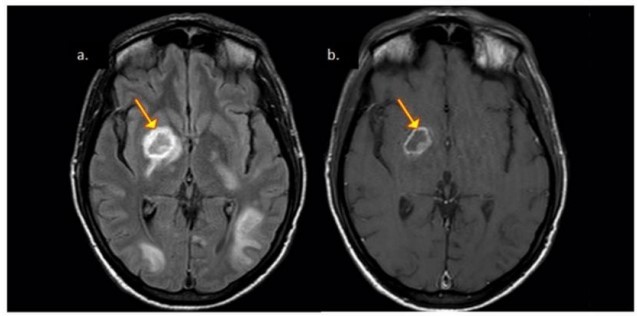

Neuroimaging reveals the presence of ring-enhancing lesions mostly seen in the basal ganglia and subcortical white matter (Fig 3). The eccentric-target and concentric-target signs are highly specific for the diagnosis of CNS Toxoplasma infection.

Fig 3: Patient with CNS toxoplasmosis. A. Axial FLAIR exhibiting hypointense lesion in the nuclei of the base with hyperintense peripheral halo (arrow). B. Axial T1 exhibiting the same hypointense lesion with peripheral ring enhancement. Mural nodule (eccentric target signal).